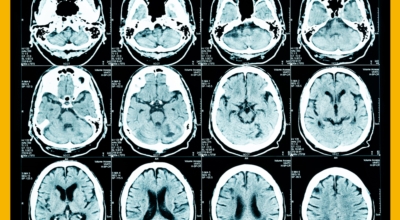

추운 겨울 날씨 속 혈관 질환 발병률이 높아지고 있습니다. 겨울철 주의해야 할 질병으로는 고혈압, 심근경색 등이 있답니다. 동맥경화증에 의해 병든 혈관에서 생기는 혈전이 심장이나 굶은 뇌동맥 등에서 떨어져 나와 말단부 뇌혈관을 막아 뇌훼손을 발생시킬 수 있답니다. 오늘 알아볼 질병은 뇌경색 초기증상입니다.

뇌 속에 혈액을 제공하는 혈관이 있는데, 이 혈관이 막히면 정상적으로 지급되어야 할 만큼의 혈액이 뇌까지 도달하지 못하여 뇌조직이 제 역할을 수행하지 못하는 것을 말해요. 이 시간이 지속될 경우 몸의 여러 곳에 지장이 생기며 이것을 뇌경색이라고 해요.

뇌경색이 발생하면 얼마나 빨리 치료를 시작할 수 있는지에 따라 예후가 결정되어요. 증상이 발생하면 최대한 빨리 병원을 방문하여 초급성기 치료를 받아야 해요. 급성기 치료 후에는 원인에 따라 재발 방지를 위한 치료를 하게 되며 후유증에 대한 재활치료도 할 수 있는 한 빨리 시행하는 것이 회복에 도움을 줘요.